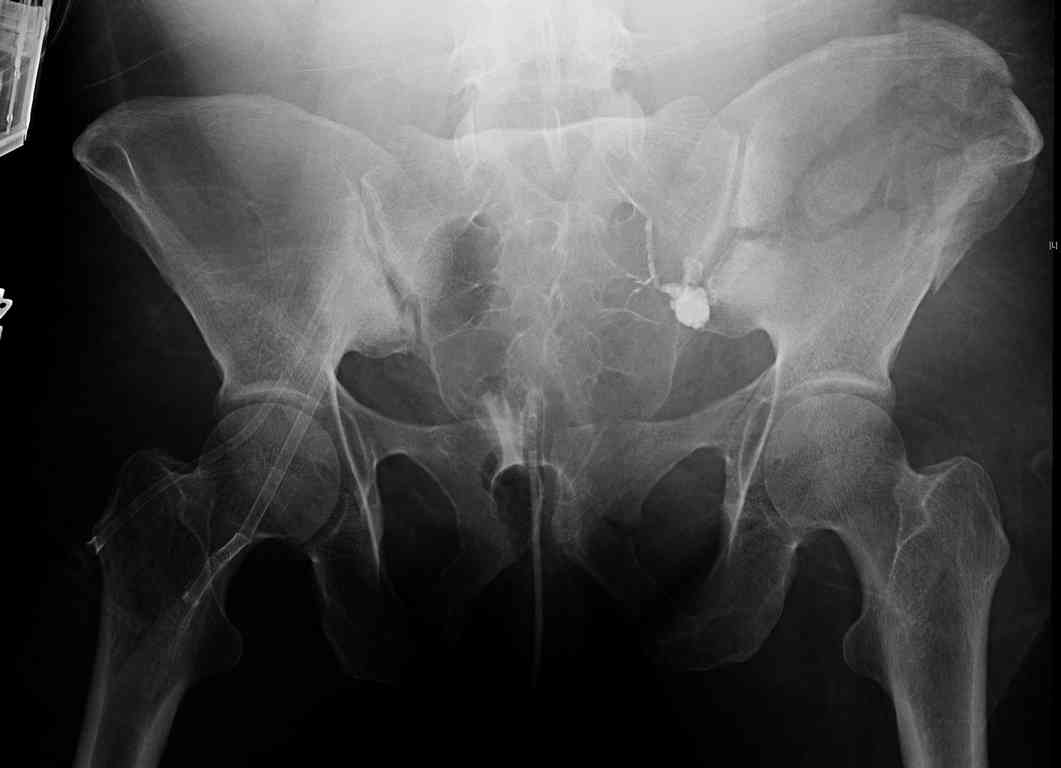

comminuted crescent fx

40 ish female ejected from car. Unstable, DPL negative, went to angio and had her pelvic bleeds embolized after many units of blood. GCS 6, floating elbow, clavicle, bothbones, etc.

My standard approach to this pelvis would be posterior, reduce/lag/plate thecrest, reduce/plate the caudal extent on the posterior crest and 1-2 lags back to front. In this case, the crest comminution seems to make plating all the way to the ASIS useless, as the plate would be on free floating fragments. Would plating the posterior extent of the fracture to secure the reduction at the SI joint and 2 screws back to front be sufficient fixation? Would anyone do a perc reduction and perc back to front screws, and would that be sufficient if the SI joint could be reduced (although I don't see how this could be accurately reduced closed). Would an ilioninguinal with a pelvic brim plate and posterior column screws be a better approach, although reducing the SI would be more indirect and less accurate?